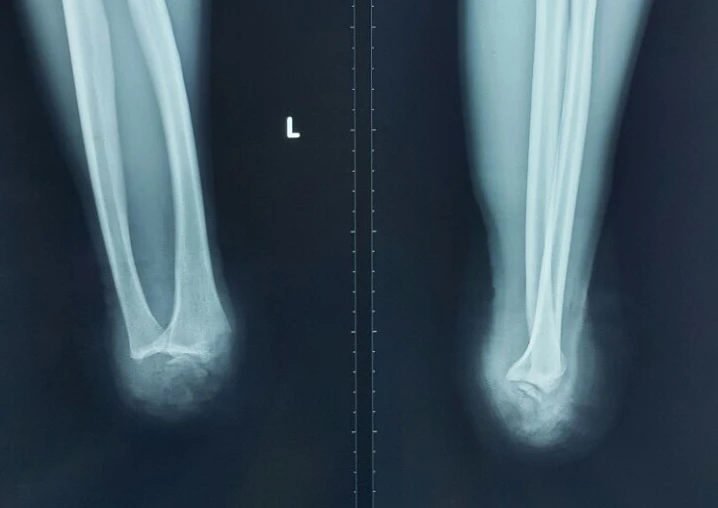

Kết quả chụp X quang cho thấy bàn tay trái anh T bị đứt lìa. Ảnh: HÒA KHÁNH